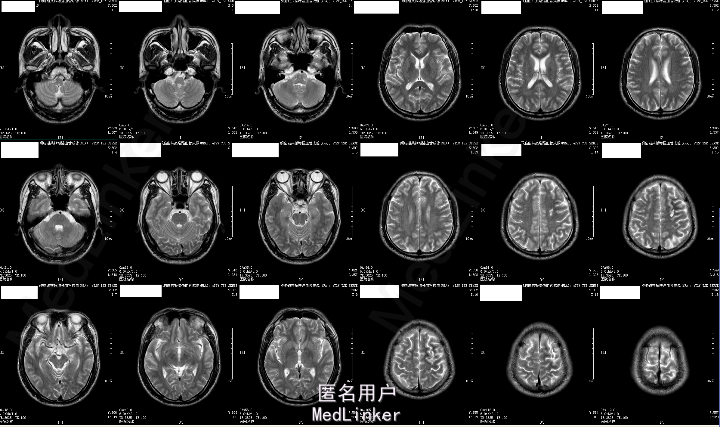

2015-05-26外院头颅MR:1.左额叶、枕叶病变考虑感染性病变可能性大(曼氏裂头蚴感染?)2.双侧上颌窦、筛窦慢性炎症。

2015-6-01我院头颅MRA:1.左侧额叶、枕叶及左侧基底节尾状核多发异常信号,考虑寄生虫感染(曼氏裂头蚴感染?)可能性大;2.左侧大脑前动脉A1段起始部稍狭窄;3.双侧筛窦炎症。

患者今年4月份时有吃“田螺、黄鳝”病史,既往有“高血压、糖尿病”,未规律治疗,结合其临床表现及头颅MRA“钻隧道”样改变,目前考虑“曼氏裂头蚴感染”可能性大。

成的中枢神经系统寄生虫病。I临床较为少见,易误诊。一般认为感染该病的途径有以下几种:食生或半生的蛙肉、蛇肉等(含裂头蚴);带有伤口的皮肤敷贴感染的生蛙皮、蛙肉等;饮用了含剑水蚤的生水。脑裂头蚴病的临床表现因感染部位的不同而各异。多以头痛、癫痫大发作及肢体活动障碍等为主,严重者可致颅内高压、视力损害、意识障碍甚至突然死亡。脑脊液检查可有蛋白及细胞数轻度升高。儿童脑裂头蚴病的病程一般不长,有些因虫体的迁延,其症状和体征也会发生改变。该病影像学表现多为单侧受累的单发病灶。病灶多位于皮质,也可侵犯脑室、脑干和小脑。活的虫体在脑内活动形成隧道、虫体分泌的产物及虫道周围的炎性反应使得该病影像学上具有一定特点:(1)主病灶一般较小,直径小于2 cm;(2)局部常伴发炎性反应,病灶周围脑实质可见不规则大片状水肿影;(3)MRI检查多表现为混杂长T1、长T2信号,临近侧脑室可变大,即所谓的“负效应”,增强扫描可见病灶呈匍行管状、串珠状、绳结状、扭曲条索状强化;(4)不同时期的影像学检查,病灶可在不同的部位;(5)CT检查可见点状钙化影,虽脑MRI对于钙化的显影不如CT,但也可表现出不均匀信号。脑裂头蚴病的病理学表现具有一定特点,裂头蚴幼虫在脑内迁徙游走形成坏死隧道,同时释放蛋白酶毒素溶解周围组织引起炎性反应,周围脑组织坏死后,局部炎性细胞浸润和纤维胶质细胞增生形成炎性肉芽肿。肉芽肿内可见有一条或数条虫体,虫体不分节,实体、无体腔,具有特征性的体壁结构是散在分布的椭圆形石灰小体及束状纵行肌纤维,前者可能为虫体的残骸。裂头蚴抗体血清免疫学检查(ELISA法)具有高度的特异性和敏感性。手术摘除裂头蚴为该病最有效的治疗手段,可